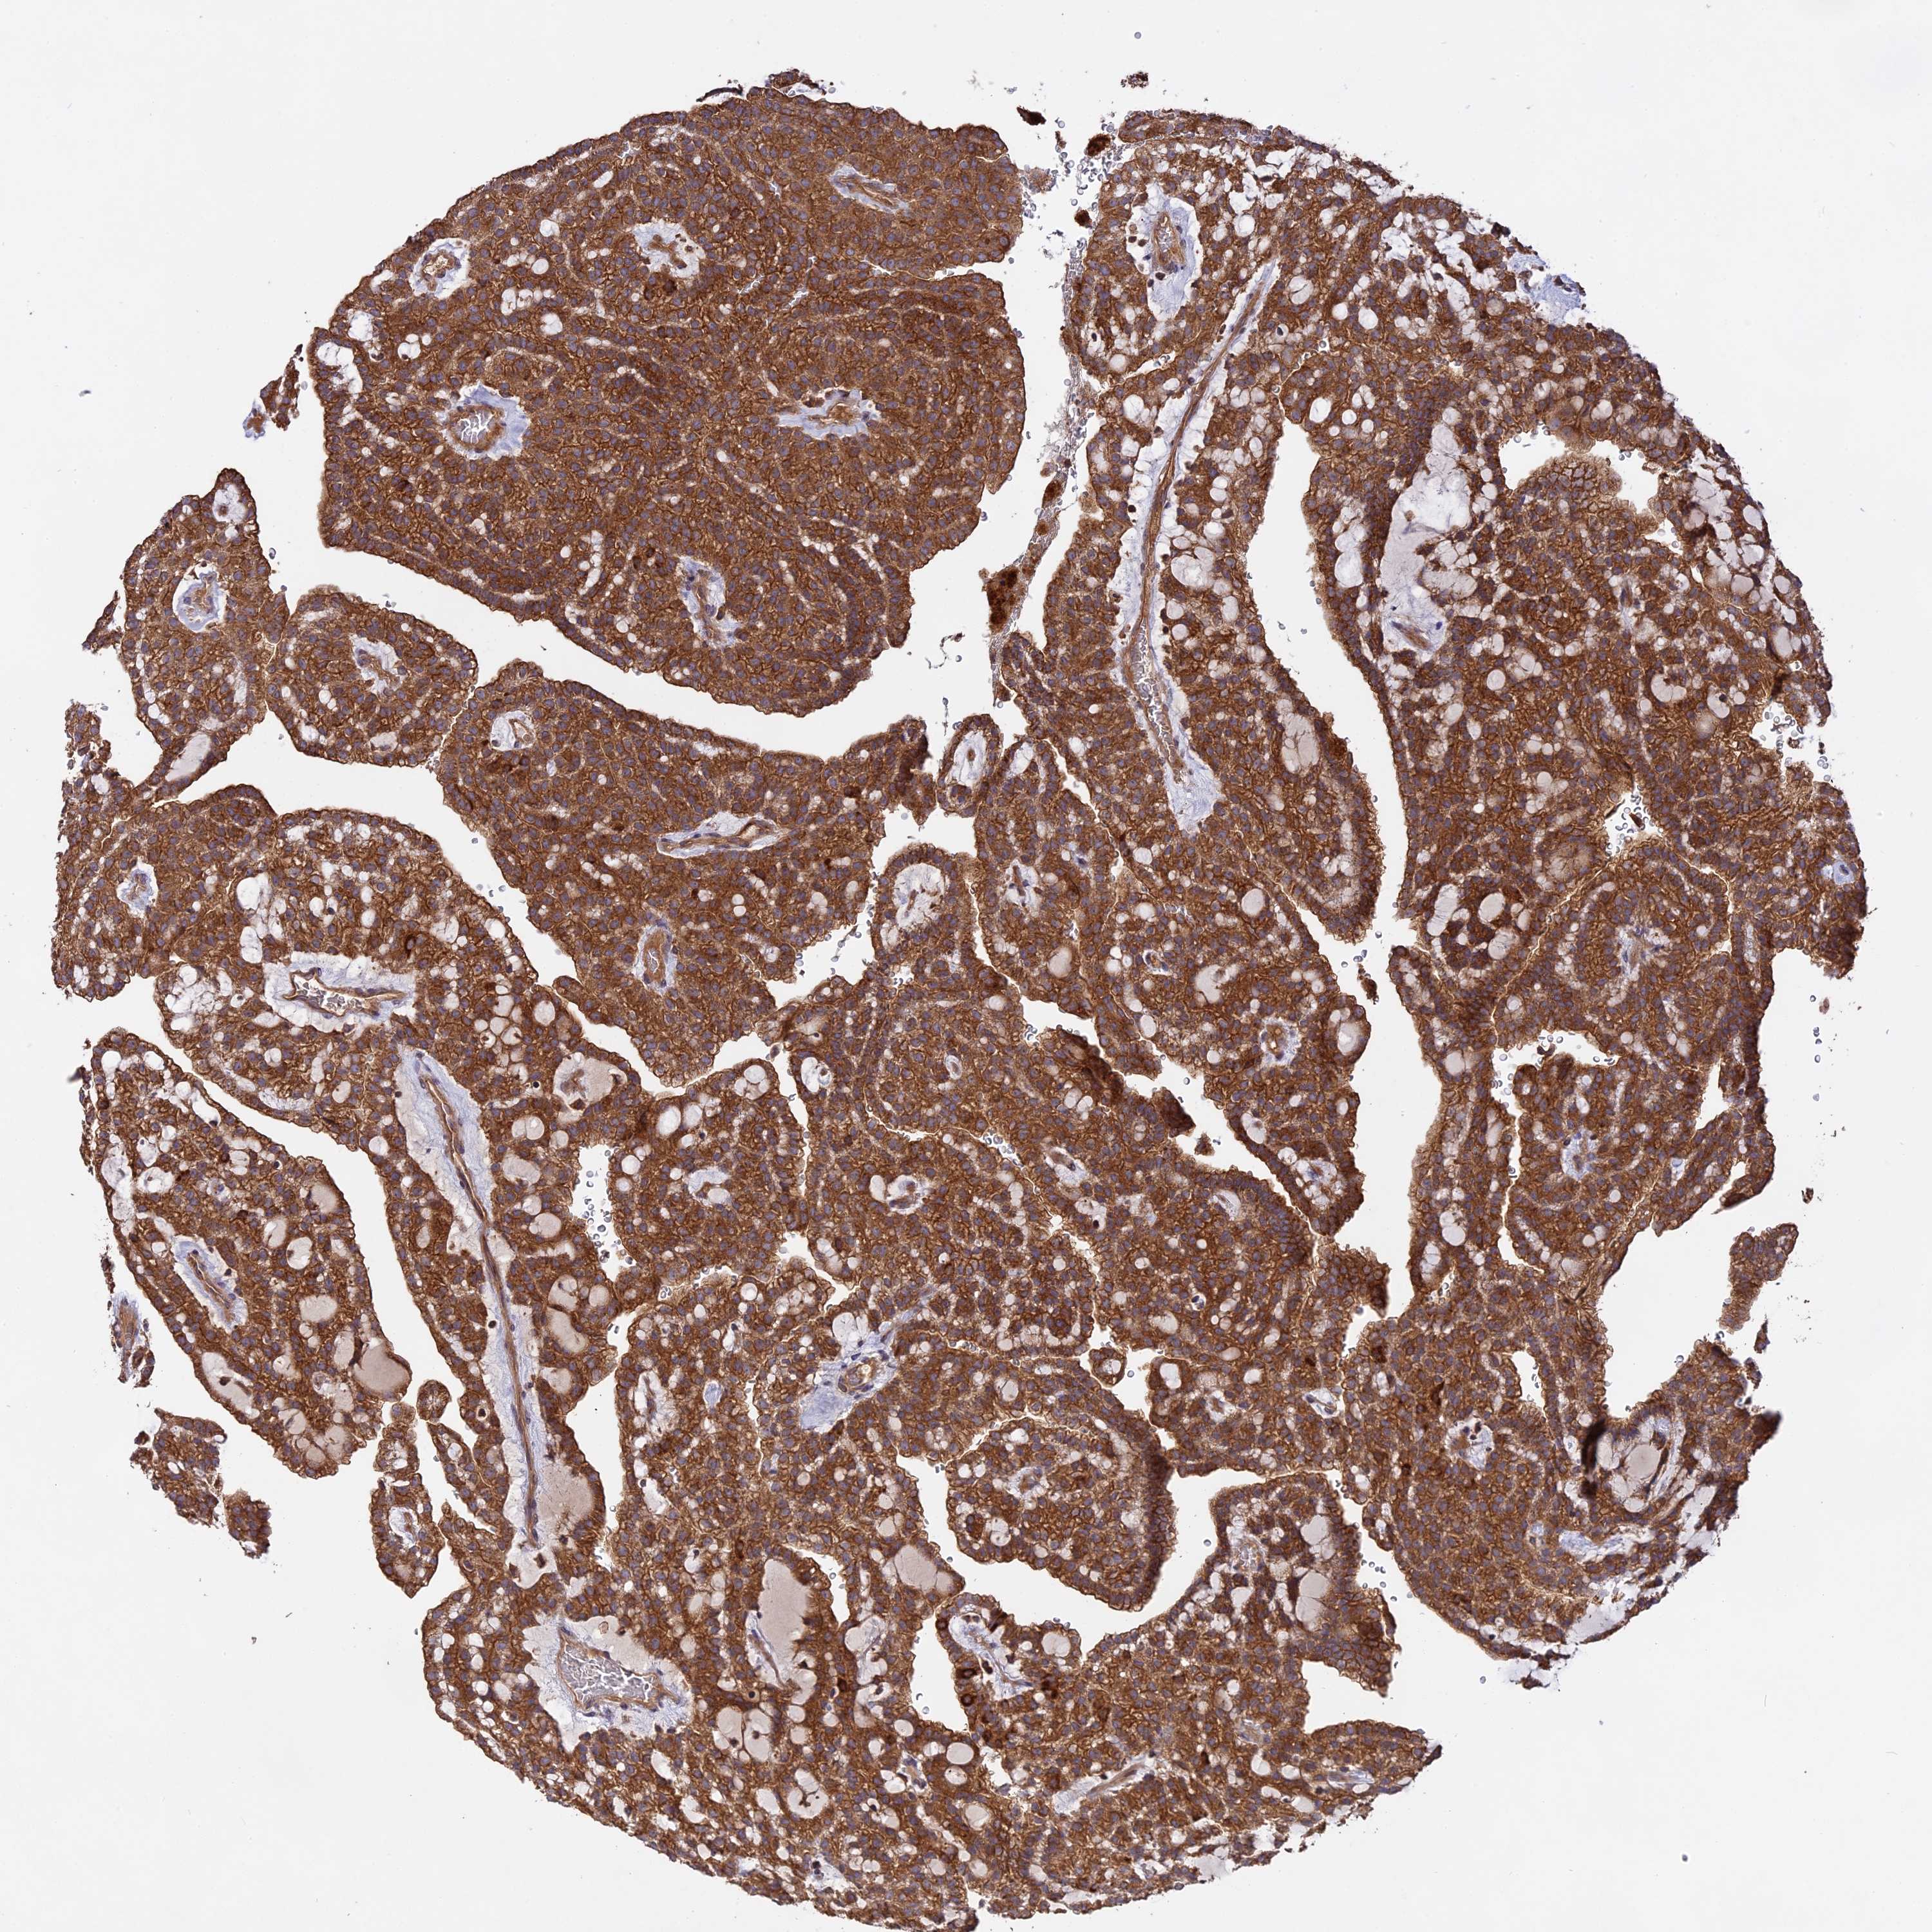

KIDNEY RENAL CLEAR CELL CARCINOMA (TCGA) - Interactive survival scatter ploti

The Survival Scatter plot shows the clinical status (i.e. dead or alive) for all individuals in the patient cohort, based on the same data that underlies the corresponding Kaplan-Meier plots. Patients that are alive at last time for follow-up are shown in blue and patients who have died during the study are shown in red.

The x-axis shows the expression levels (FPKM) of the investigated gene in the tumor tissue at the time of diagnosis. The y-axis shows the follow-up time after diagnosis (years). Both axes are complimented with kernel density curves demonstrating the data density over the axes. The top density plot shows the expression levels (FPKM) distribution among dead (red) and alive patients (blue). The right density plot shows the data density of the survived years of dead patients with high and low expression levels respectively, stratified using the cutoff indicated by the vertical dashed line through the Survival Scatter plot. This cutoff is automatically defined based on the FPKM cutoff that minimizes the p-score. The cutoff can be changed by dragging the vertical line or by entering a cutoff value in the square labeled "Current cut-off".

Under the Survival Scatter plot the p-score landscape (black curve; left axis) is shown together with dead median separation (red curve; right axis). Dead median separation is the difference in median mRNA expression between patients who have died with high and low expression, respectively. It is calculated as follows: median FPKM expression of dead patients with high expression - median FPKM expression of dead patients with low expression. This is intended to aid the user in visually exploring custom cutoffs and the associated p-scores and dead median separation.

Individual patient data is displayed and can be filtered by clicking on one or more of the category buttons on the top of the page. Categories describing expression level and patient information include: high, low, alive, dead, female, male and tumor stages. The scale of the x-axis can be toggled between linear and log-scale by clicking on the "x log" button. Mouse-over function shows TCGA ID, patient information and mRNA expression (FPKM) for each patient.

& Survival analysisi

Kaplan-Meier plots summarize results from analysis of correlation between mRNA expression level and patient survival. Patients were divided based on level of expression into one of the two groups "low" (under cut off) or "high" (over cut off). X-axis shows time for survival (years) and y-axis shows the probability of survival, where 1.0 corresponds to 100 percent.

NUDT8 is not prognostic in Kidney Renal Clear Cell Carcinoma (TCGA)

Best expression cut offi

Based on the FPKM value of each gene, patients were classified into two groups and association between prognosis (survival) and gene expression (FPKM) was examined. The best expression cut-off refers the FPKM value that yields maximal difference with regard to survival between the two groups at the lowest log-rank P-value. Best expression cut-off was selected based on survival analysis .

When clicking on this number, the vertical dashed line indicating cut-off, the interactive survival plot, and the Kaplan-Meier curve will be adjusted to show results based on the best expression cut-off.

: 8.47

Median expressioni

Median expression refers to the median FPKM value calculated based on the gene expression (FPKM) data from all patients in this dataset. When clicking on this number, the vertical dashed line indicating cut-off, the interactive survival plot, and the Kaplan-Meier curve will be adjusted to show results based on the median expression.

: N/A

Median follow up timei

Median follow up time refers to the median time (years) after diagnosis with this type of cancer, based on clinical data from all patients in this dataset.

P scorei

Log-rank P value for Kaplan-Meier plot showing results from analysis of correlation between mRNA expression level and patient survival.

N/A

5-year survival highi

5-year survival for patients with higher expression than the expression cutoff.

For melanoma and glioma, 3-year survival is shown.

5-year survival lowi

5-year survival for patients with lower expression than the expression cutoff.

TCGA RNA samplesi

RNA-seq data is reported as average FPKM (number Fragments Per Kilobase of exon per Million reads), generated by the The Cancer Genome Atlas (TCGA) .

Normal distribution across the dataset is visualized with box plots, shown as median and 25th and 75th percentiles. Points are displayed as outliers if they are above or below 1.5 times the interquartile range. FPKM values of the individual samples are presented next to the box plot.

Average pTPM 14.3

Number of samples 521